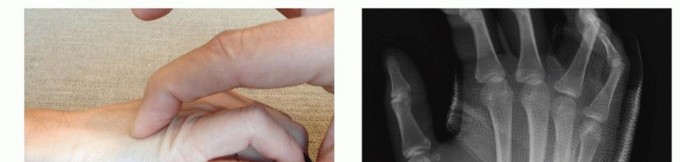

A rigorous, systematic clinical assessment is the first step in preoperative planning. Inspection must evaluate the hand at rest, noting the natural digital cascade, and through a full active arc of motion. The surgeon must critically assess for any deviation of the nail beds during flexion, the hallmark of rotational malalignment. Palpation should trace the dorsal contour of the metacarpals to identify fracture step-offs, while simultaneous volar palpation assesses for symptomatic metacarpal head prominence. The surgeon must maintain a high index of suspicion for associated injuries, meticulously examining the skin for subtle puncture wounds over the MCP joints that signify a human tooth strike, and evaluating the CMC joints for subtle subluxations that frequently accompany basilar fractures.

Clinical & Radiographic Imaging Archive